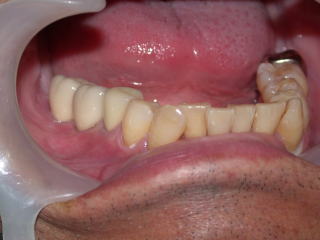

症例11、60才代男性(新潟県長岡市要町 要町歯科歯科 インプラント)

右下6番、7番にインプラントを稙立し、白い被せものを入れました。

奧の白い2本の歯です。

稙立は2021年2月16日です。

上部構造物(白い歯)の装着は2021年8月11日です。